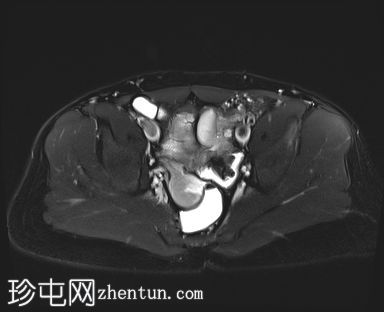

MRI

轴位

STIR

MRI图像显示子宫和睾丸。子宫内膜腔开口于前列腺尿道。

患者有双侧隐睾病史。CT和MRI图像显示发育良好的子宫和两个睾丸,均位于盆腔内。子宫内膜腔开口于前列腺尿道。

该患者表型为男性,阴茎发育良好。精液分析显示无精子症。结合影像学检查结果,最可能的诊断是持续性苗勒氏管综合征。这是一种男性假两性畸形,由子宫内抗苗勒氏管激素(AMH)分泌不足引起。AMH或其信号通路的缺乏导致苗勒氏管衍生结构的持续发育。